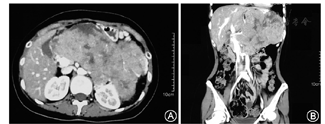

考虑肿瘤巨大(图1),且具有内分泌功能,为缓解神经系统症状及解除肿瘤占位压迫症状,于2016年4月11日行手术治疗。术中见肿物位于小网膜囊内,与胃后壁粘连致密,左侧与胰腺体尾部关系密切并侵犯脾血管,右侧累及肝十二指肠韧带,上达膈下,下方挤压左肾脏并侵犯左侧肾上腺。术中遵循"整块原则"、"无瘤原则",将肿物连同周围的胰腺体尾部、脾脏、左侧肾上腺、部位胃一并切除。术后病理回报:胰腺混合性腺泡-神经内分泌癌(mixed acinar-neuroendocrine carcinoma,MANEC),侵及胰周脂肪组织,侵及胃壁全层,紧邻脾脏及肾上腺被膜,体积16 cm×13 cm×10 cm,AACT(+),α-抗胰蛋白酶(+),AE1/AE3(+),CD56(部分+),CgA(部分+),Syn(+),ACTH(-),促肾上腺皮质激素释放激素(corticotropin releasing hormone,CRH)(+),Ki-67(index 80%)。患者术后出现胃排空延迟,予以胃管引流和肠外营养支持后好转,Clavien-Dindo分级Ⅱ级。余情况均恢复顺利,配合激素序贯减量治疗后,神经系统症状消失,ACTH和皮质醇分别降至10.2 ng/L和14.8 μg/L,甲胎蛋白、CA125、胃泌素均恢复正常,于2016年5月25日出院。患者及家属拒绝术后辅助化疗,于门诊每3个月复查影像学检查,至2018年8月发现左肾门转移病灶,并经穿刺活检证实,目前仍带瘤生存。